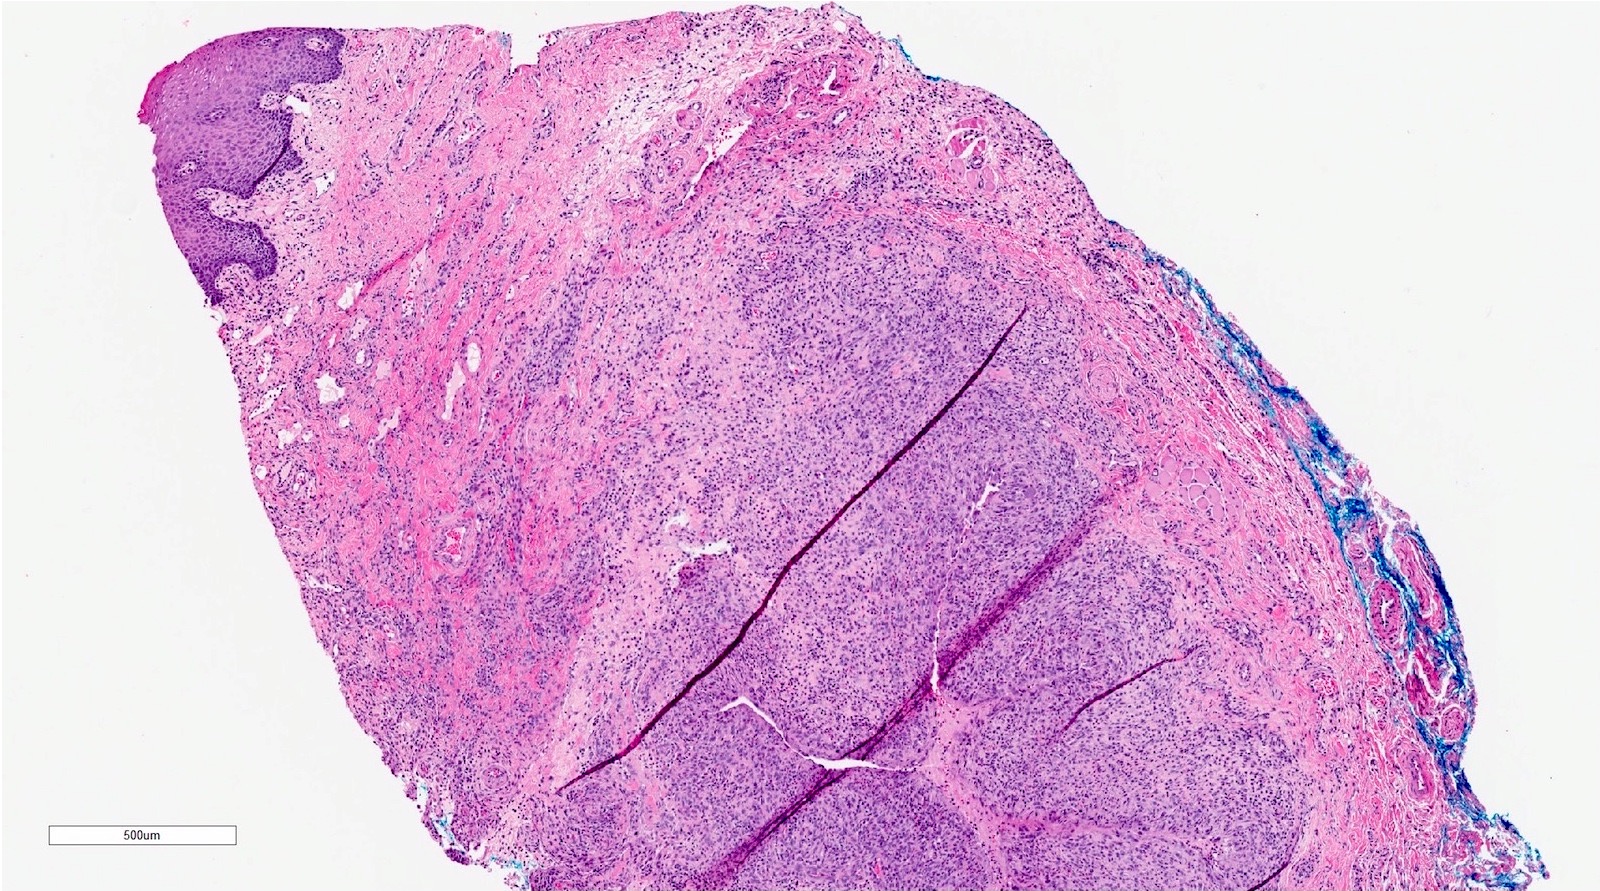

Microscopic (histologic) description

- If removed intact

- Pseudocyst cavity containing mucin, abundant epithelioid foamy histiocytes (muciphages), neutrophils and granulation tissue (Acta Histochem 2014;116:40)

- If removed ruptured

- Fragments of granulation tissue containing epithelioid foamy histiocytes (muciphages) and neutrophils, may see mucinous material (Acta Histochem 2014;116:40)

- Removed salivary gland parenchyma showing obstructive changes

- Acinar atrophy, ductal dilatation with periductal hyalinization, interstitial lymphoplasmacytic infiltrate and interstitial fibrosis at late stage (J Oral Maxillofac Surg 2008;66:2050)

- May see ruptured feeding salivary duct with squamous metaplasia (J Oral Maxillofac Surg 2008;66:2050)

- Long standing lesions organize into fibrosis resembling a fibroepithelial polyp (Acta Histochem 2014;116:40)

- No epithelial cyst lining, may see overlying surface oral mucosa with variable atrophy in superficial mucoceles (J Oral Maxillofac Surg 2011;69:1086)

Microscopic (histologic) images